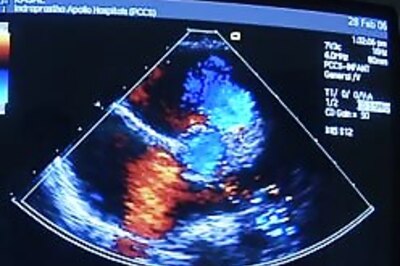

'Bad cholesterol' level lowers blockages in blood vessels open. A high dose of cholesterol drug also reverses heart disease, says study.